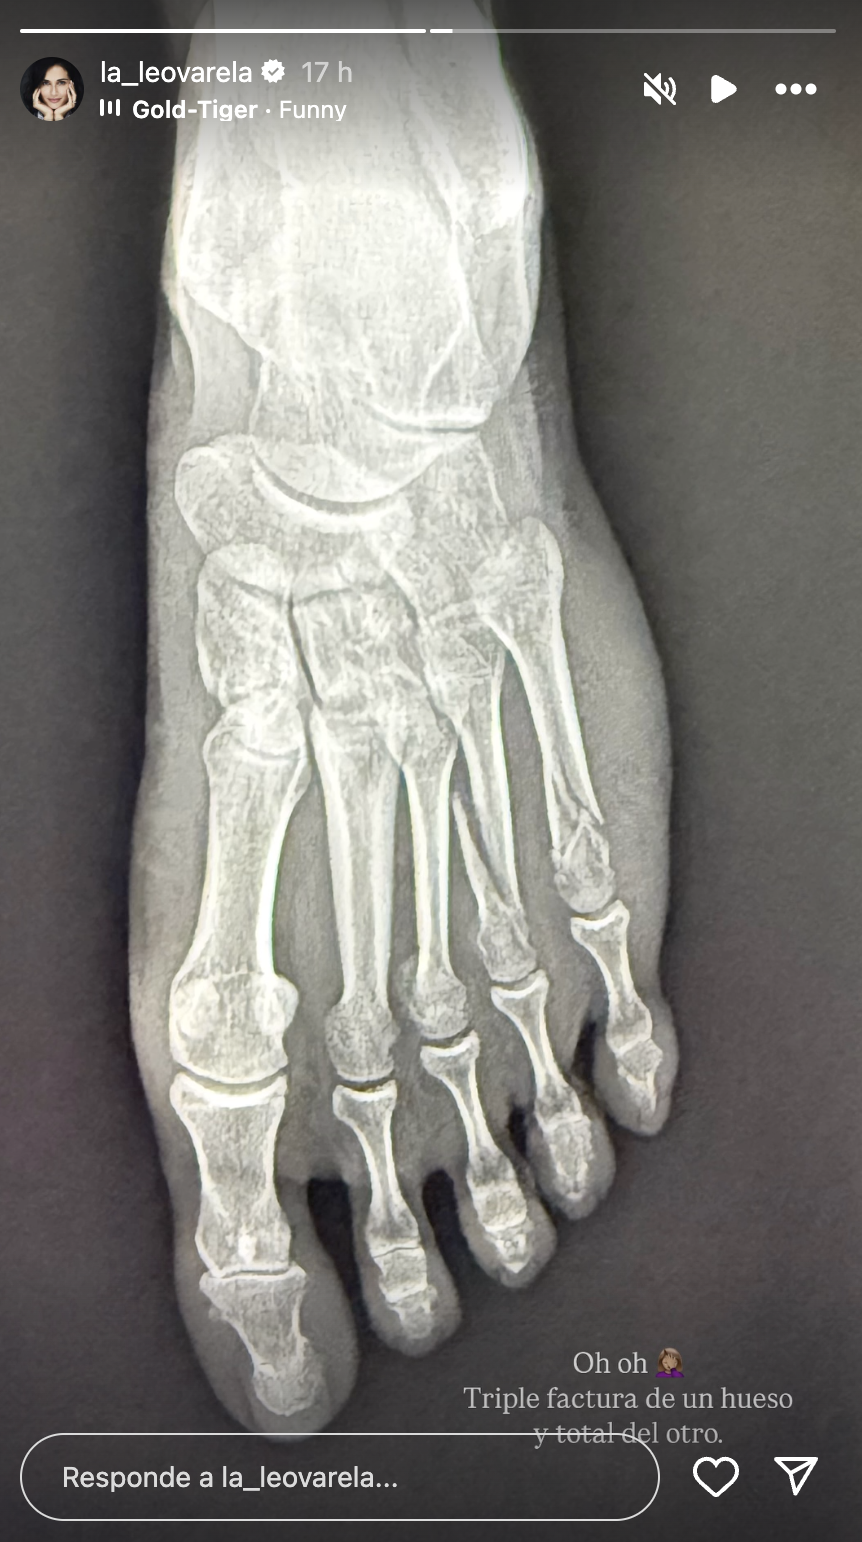

Más tarde subió una imagen de la radiografía de su pie y un lapidario diagnóstico: "Oh, oh, triple fractura en un hueso y (fractura) total en otro", escribió Varela.